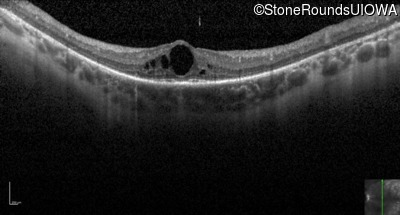

Optical Coherence Tomography - Left - 20/70 +1

Exemplar / OCT Stack